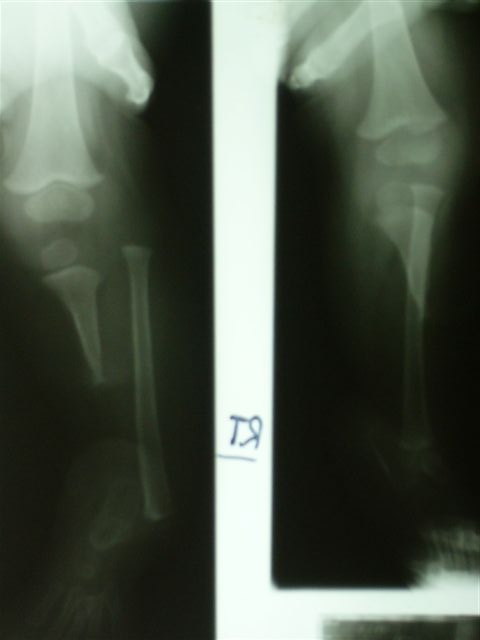

Уважаемые коллеги,Ребенок 4 лет с врожденной гемимелией б/б кости справа.

Первые две операции сделаны в годовалом возрасте - проксимальный тибио-фибулярный синостоз и транспозиция дистального отдела малоберцовой кости на таранную кость.В настоящее время - пользуется ортопедической обувью, компенсирующей 6 см укорочение конечности, нога опороспособна и безболезненна.Рг - компенсаторная гипертрофия малоберцовой кости, состоявшийся синостоз б/б и м/б.Вопрос: когда следует начинать коррекцию длины в аппарате?Заранее спасибо за рекомендацииЕвгений И Чекашкин

Сейчас ребенку 4 года, укорочение 6 см. Существует мнение о начале коррекции в аппарате не ранее 5 летнего возраста, кость становится прочнее, меньше риск миграции спиц. Хотя и на современных Рг кость выглядит вполне *зрелой*.

К сожалению, после осмотра весь пакет с Рг родители забрали с собой. Описание Рг: В принципе, голеностопного сустава (как анатомического образования) у ребенка не было сформировано, поэтому при росте м/б кости происходило * выталкивание* стопы медиально с её супинацией (начальные снимки). Поэтому, чтобы яредотвратить усугубление деформации стопы, мы решили сопоставить м/б кость с таранной и фиксировали спицами и гипсовой повязкой. На том этапе сознательно на артродез не пошли, рассчитывая, что фиброз в зоне контакта костей позволит сохранить межфрагментарную подвижность, облегчающую ходьбу, и не ошиблись. На данный момент подвижность в зоне контакта малоберц.-таранная костей в пределах 30 градусов (пассивные движения) активные практически отсутствуют, можно думать и о мышечной аномалии- выражены только сгибатели и пронаторы стопы.